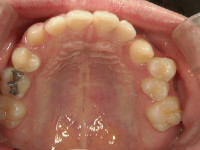

顎顔面矯正治療では、急速拡大装置という特殊な装置を使って、歯だけでなく顎の骨自体を矯正していきます。

顎の骨が広がれば、歯は正しい位置へ自然に収まり、歯並びも美しくなります。

~顎顔面矯正治療で骨格から美しい歯並びに~